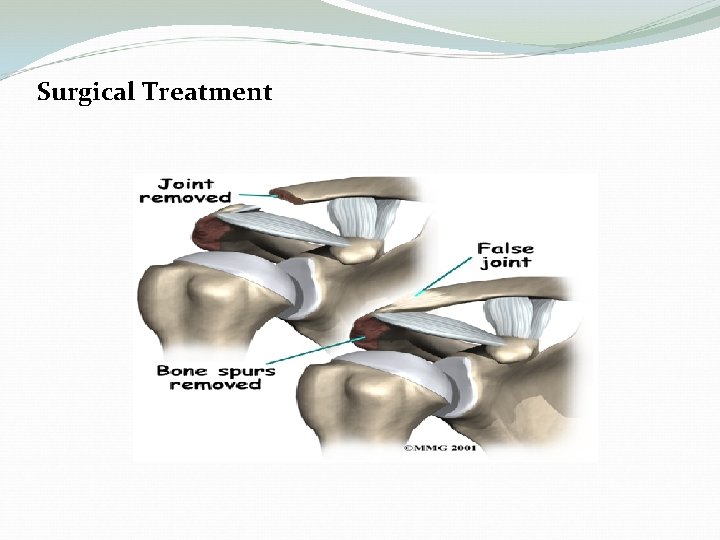

Surgical Treatment